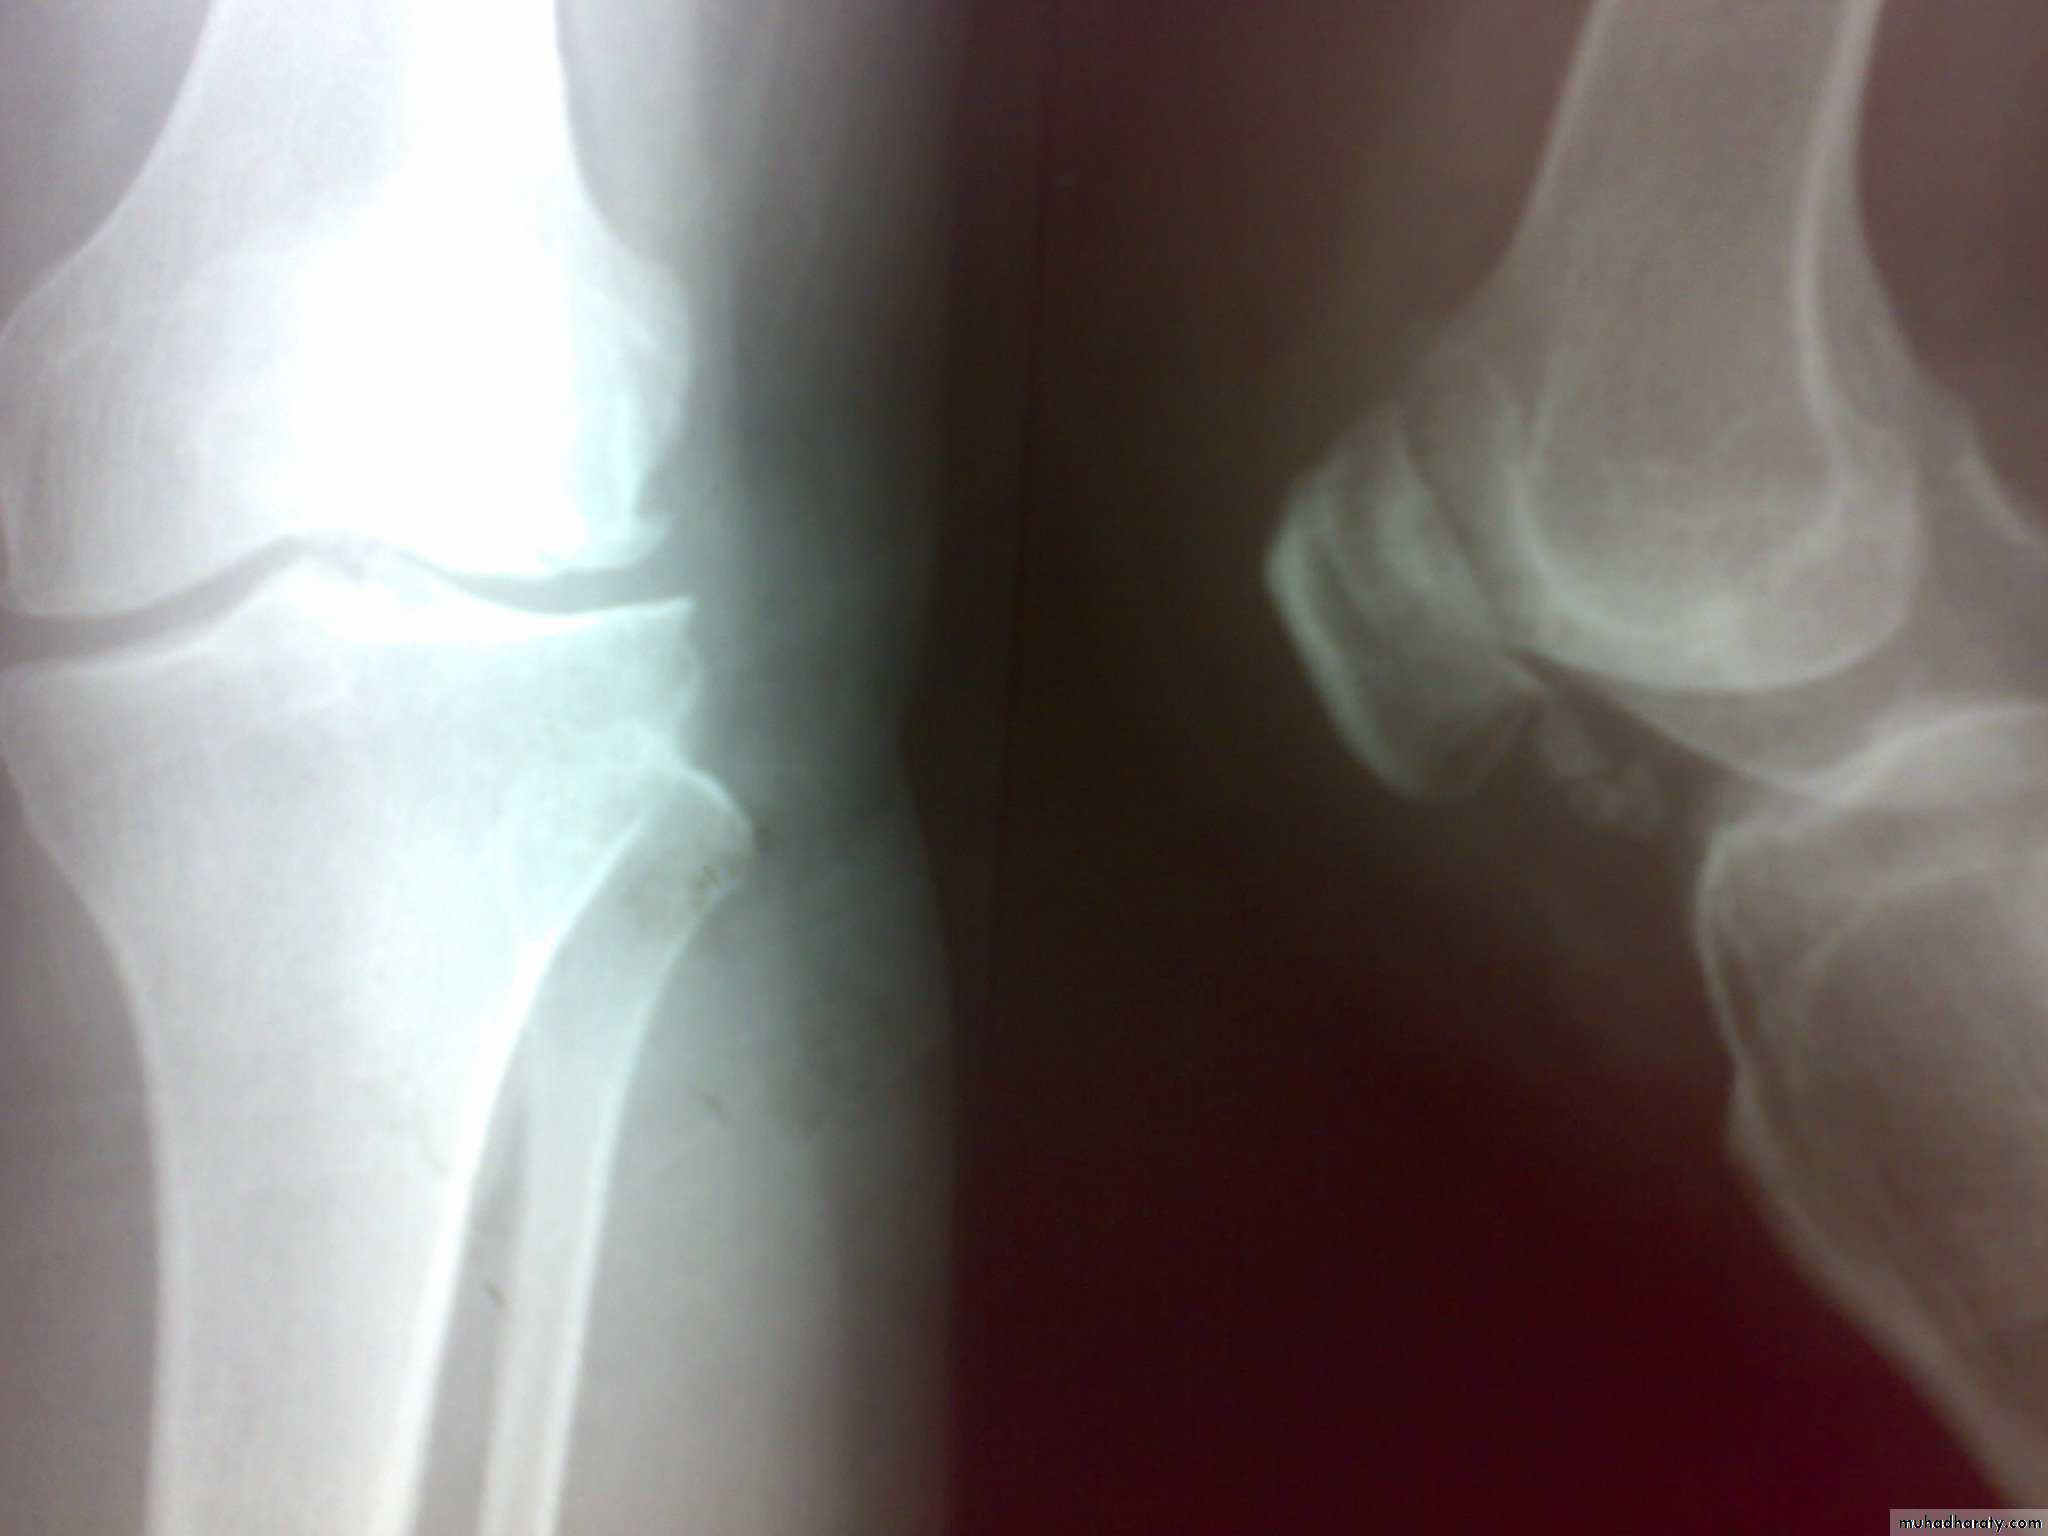

Dx of gout is established by Monosodium urate crystals viewed under the polarizing microscope. X-ray demonstrating typical gouty erosions at the first MTP joint, with well-demarcated erosions, away from the joint line, some with overhanging edges, and adjacent hazy tophaceous material.

-Radiograghs which is :

a-Normal in early stage

b-Later :joint space narrowing ,sclerosis,cyst, osteophyte and gouty erosions( para articular punched out defects)